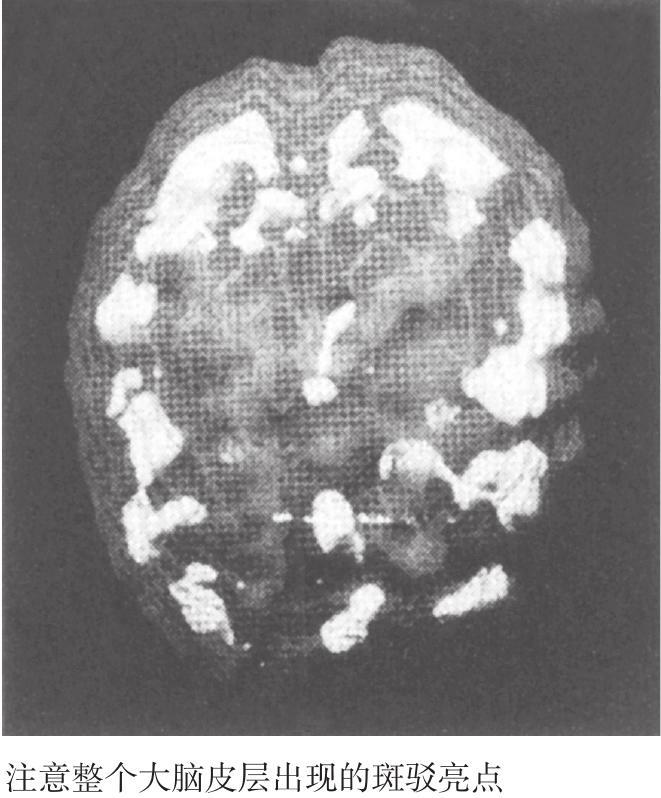

图2-2 萨拉受到躁狂抑郁症影响的大脑3D图

要对她进行脑部扫描并不是一件容易的事。临床大夫尝试了三次。前两次她都拔掉了静脉注射管,并大声说我们想毒死她。第三次,她的妹妹和她交谈后令她放松下来,这一次终于成功了。当扫描结果显示出她的深层边缘系统整体上存在过度激活时,我发现她左侧的大脑激活程度更高,即深层边缘系统有非常集中的焦点,并且整个大脑皮层都出现了明显的斑驳亮点(见图2-2)。换句话说,萨拉的一部分脑区显示出了过度激活,而另一部分脑区则呈现出抑制的状况。经验告诉我,周期性心境障碍通常都会和这种情况有关。